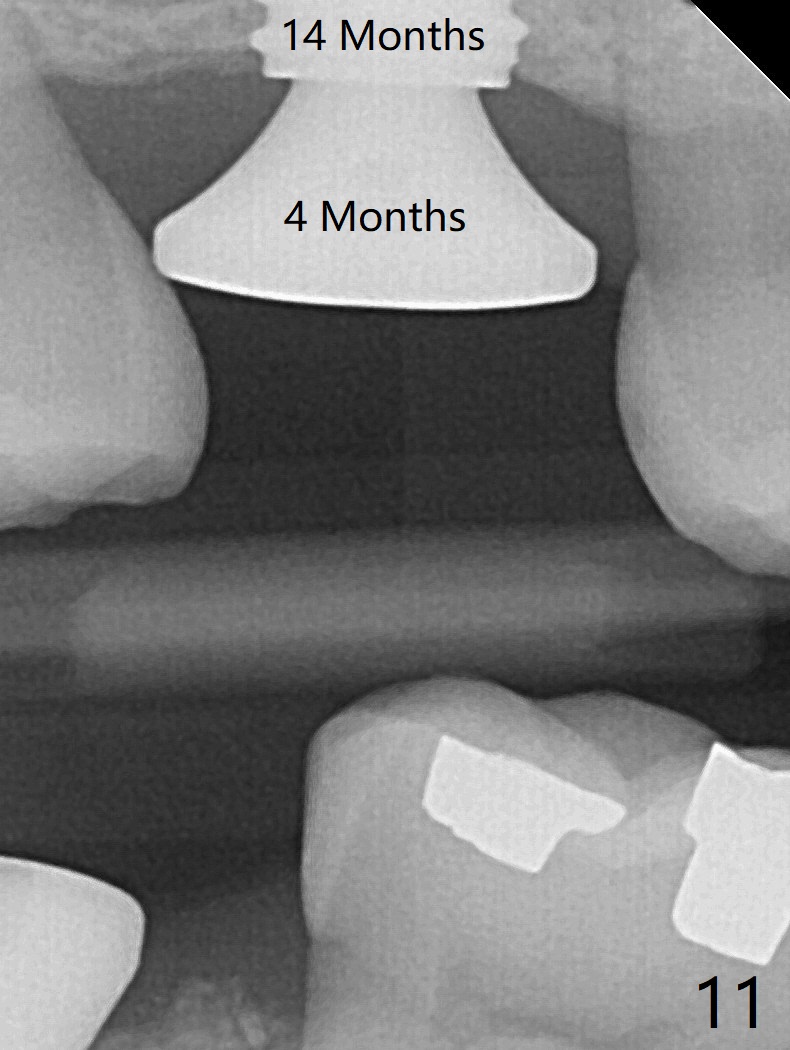

When the residual roots of the tooth #3 are removed, there is a gingival band over the septum (Fig.1 S). Osteotomy (Fig.2 yellow circle) would tear it off. To save the soft tissue, the buccal attachment is severed (Fig.3 black line), the flap is rotated palatal (Fig.3 curved arrow) and sutured in place (Fig.5 S). After sinus floor breakdown (use of sinus drill for 16 mm) and use of membrane lifter/water, two pieces of PRF membrane are inserted. The membrane is so slippery that it is easy to enter the sinus for further sinus membrane lift and later allograft placement (Fig.4 *). A 4.5x10 mm dummy implant is placed with high torque after 4x7.3 mm drill with 3 mm stopper so that 4.5x7.3 mm drill with 1 mm stopper is used before placement of a 5x8.5 mm final implant with ~ 35 Ncm (Fig.5-7). The patient reports anterior sinus wall tenderness with right nasal discharge a few days postop. The provisional has mobility without tenderness 1 week postop. It appears that the sinus membrane has been involved, which is quickly repaired probably by PRF. There is no pain when a 5.2x4(2) mm cemented abutment is torqued at 30-35 Ncm before impression (Fig.8). The surrounding soft tissue is healthy. When the permanent crown is delivered, the patient feels light pain when she bites hard. The discomfort persists 4 months post cementation (Fig.9). The crown/abutment is replaced with a healing abutment (Fig.10). There is no bone loss 4 months post healing abutment placement (14 months post implant placement, Fig.11). Upper Molar Immediate Implant, Prevent Molar Periimplantitis (Protocols, Table), Trajectory II, 31 Flap Not Transferred Xin Wei, DDS, PhD, MS 1st edition 07/26/2019, last revision 10/05/2020